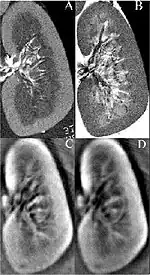

Thermoacoustic imaging was originally proposed by Theodore Bowen in 1981 as a strategy for studying the absorption properties of human tissue using virtually any kind of electromagnetic radiation.[1] But Alexander Graham Bell first reported the physical principle upon which thermoacoustic imaging is based a century earlier.[2] He observed that audible sound could be created by illuminating an intermittent beam of sunlight onto a rubber sheet. Shortly after Bowen's work was published, other researchers proposed methodology for thermoacoustic imaging using microwaves.[3] In 1994 researchers used an infrared laser to produce the first thermoacoustic images of near-infrared optical absorption in a tissue-mimicking phantom, albeit in two dimensions (2D).[4] In 1995 other researchers formulated a general reconstruction algorithm by which 2D thermoacoustic images could be computed from their "projections," i.e. thermoacoustic computed tomography (TCT).[5] By 1998 researchers at Indiana University Medical Center[6] extended TCT to 3D and employed pulsed microwaves to produce the first fully three-dimensional (3D) thermoacoustic images of biologic tissue [an excised lamb kidney (Fig. 1)].[7] The following year they created the first fully 3D thermoacoustic images of cancer in the human breast, again using pulsed microwaves (Fig. 2).[8] Since that time, thermoacoustic imaging has gained widespread popularity in research institutions worldwide.[9][10][11][12][13][14][15] As of 2008, three companies were developing commercial thermoacoustic imaging systems – Seno Medical,[16] Endra, Inc.[17] and OptoSonics, Inc.[18]

- ^ Kruger RA, Kopecky KK, Aisen AM, Reinecke DR, Kruger GA, Kiser Jr W. Thermoacoustic computed tomography – a new medical imaging paradigm Radiology 1999,211:275-278.